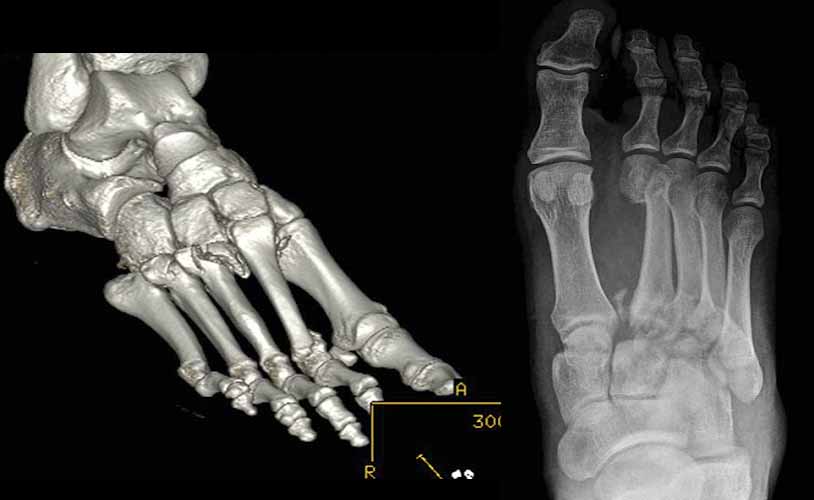

Imatge de radiografia convencional (dreta) i TAC (esquerra) d’unes fractures que afecten l’anomenada articulació de Lisfranc, que comprèn les articulacions del mitjà peu entre les cuixes i els metatarsians. Es tracta de fractures desplaçades que requeriran cirurgia.